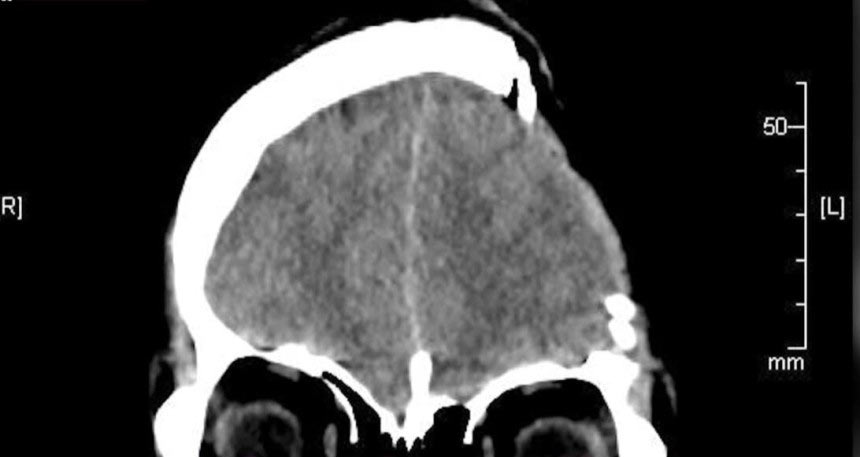

頭蓋骨の一部を失った韓国の元CAユーチューバー、悪質コメントにも笑顔でいられる理由とは(1/2)